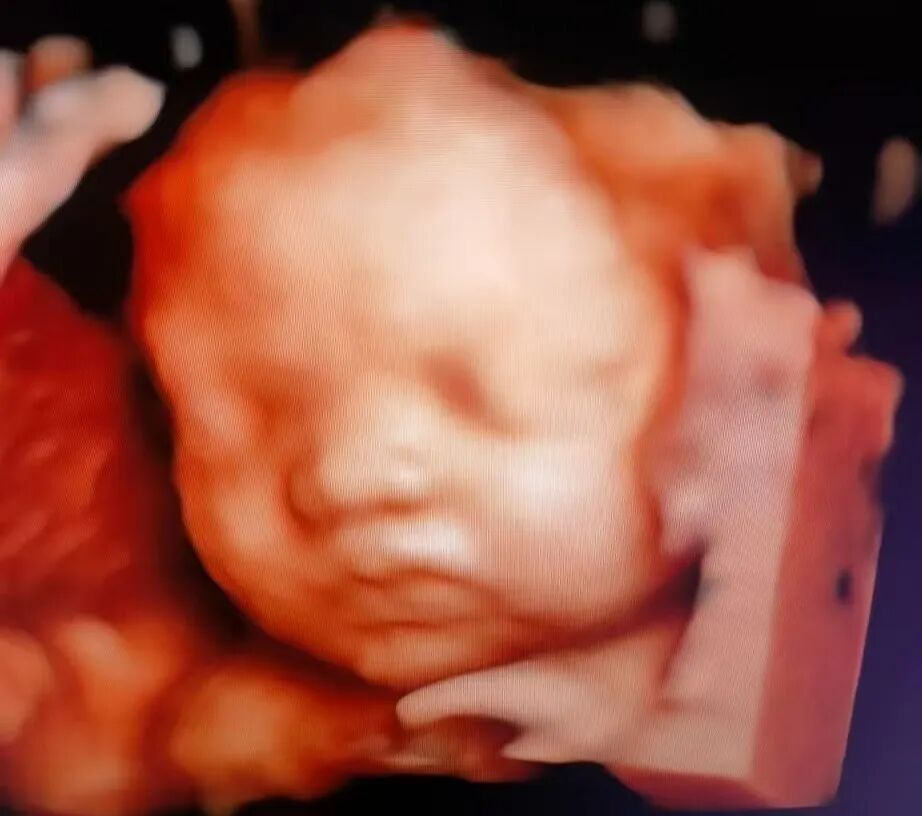

做四维彩超,本是孕期最令人期待的时刻之一——终于可以清晰地看到宝宝的小模样了!小家伙却常“闹小脾气”:睡觉、捂脸、背对镜头...就是不摆“完美pose”。

海南菁华生殖妇产医院B超室的医师们天天和“小调皮”打交道,今天就来给大家支支招,让您和宝宝的第一次“清晰会面”更顺利!

掌握了这些实用小妙招,再配合海南菁华生殖妇产医院B超室医师们的专业护航,让宝宝“配合”不再难!经验丰富的他们深谙与“小调皮”的周旋之道,操作准确轻柔,还会特别预留充足时间,运用先进设备,清晰捕捉宝宝每一帧珍贵影像,守护您与宝宝的清晰初见!